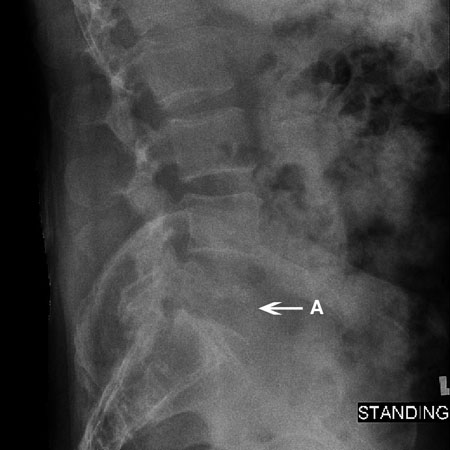

Si se produce una fractura por compresión mediante un mecanismo de baja energía, se deben encontrar las razones metabólicas de la fractura, y hay que tratar la osteoporosis agresivamente para prevenir fracturas posteriores.[Figure caption and citation for the preceding image starts]: Radiografía de una fractura por compresión: radiografía lateral de una fractura por compresión de L2 (A). Se observa el acuñamiento del cuerpo vertebralCortesía del Dr. K. Singh; usado con autorización [Citation ends].